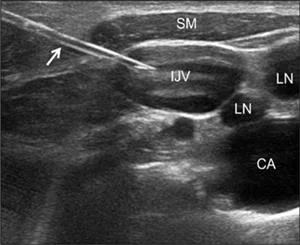

• Vascular Access